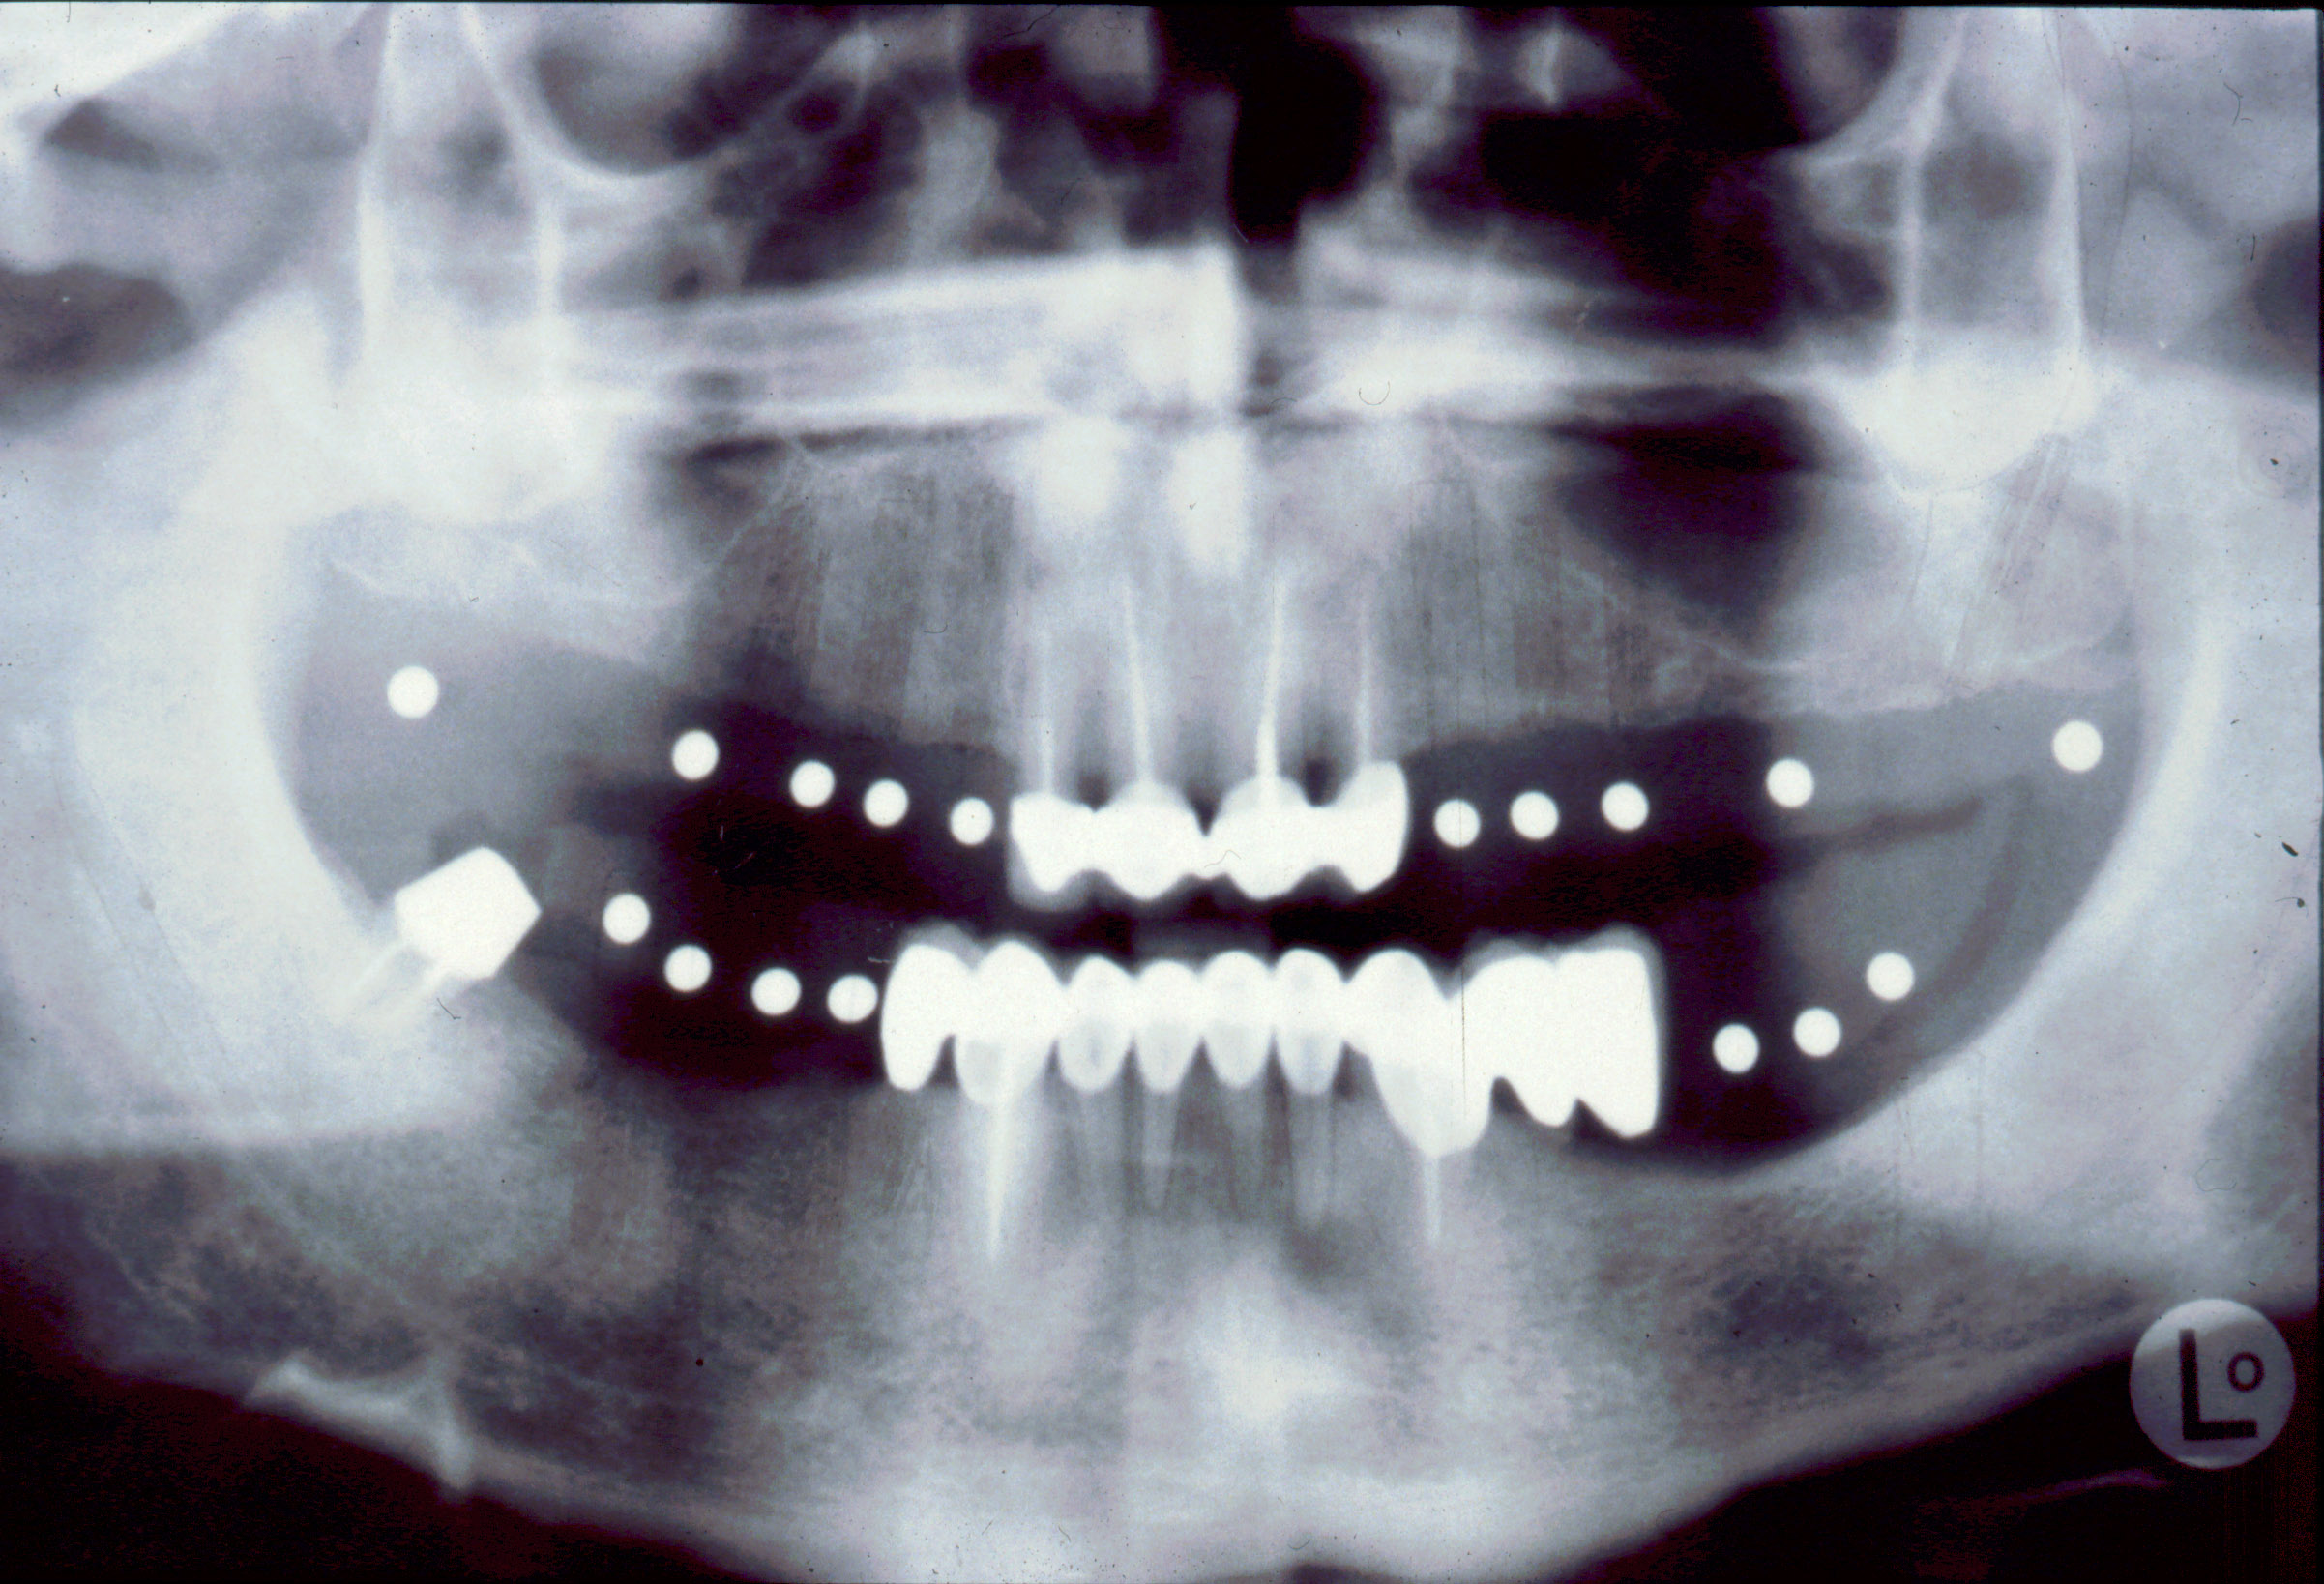

El paciente fue tratado en el año 1994 con una rehabilitación oral. Se instalaron 10 implantes métrica de rosca de conexión 2,3mm : 6 en maxilar superior y 4 en maxilar inferior. En maxilar superior se instalan 3 en segmento distal derecho y 3 en segmento distal izquierdo y permanecen 4 dientes incisivos anteriores superiores como remanente. Con estos 10 apoyos en maxilar superior (3 implantes +4 dientes+3 implantes) se instala una arcada ceramo–metálica superior por segmentos (3+4+3). En mandíbula se instalan 4 implantes en zona distal inferior derecha y una prótesis ceramo–metálica en segmento individual sobre estos 4 implantes, el resto son dientes naturales con coronas ceramo–metálica. Todos los aditamentos utilizados fueron rectos macizos originales de la marca utilizada en aquel momento (titanio grado 3). Así de este modo se realiza la rehabilitación oral.